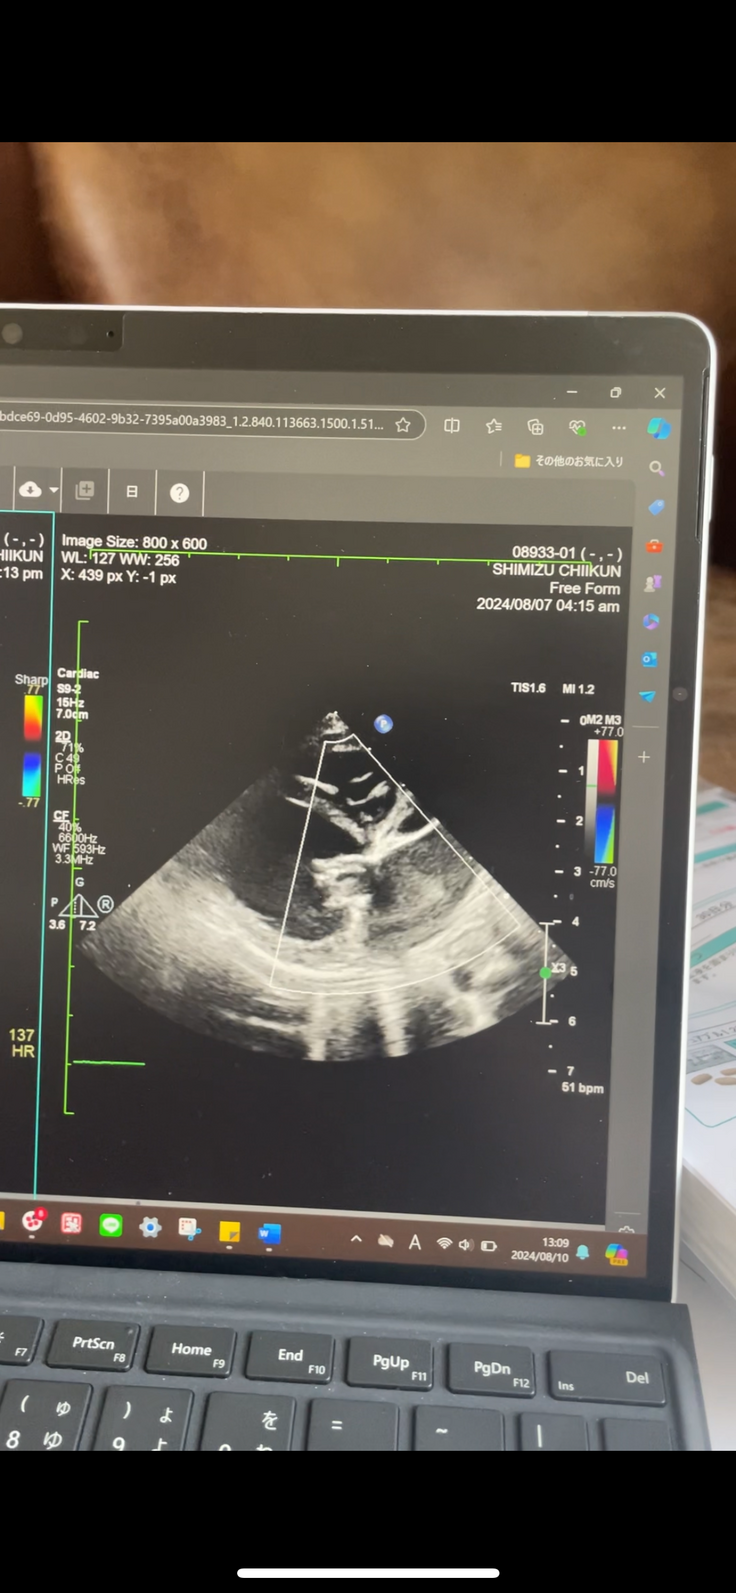

エコー画像ビフォーアフター

チーくんの心臓病(僧帽弁閉鎖不全症)エコー画像、術前と術後の比較です

↑↑ 一方術後です。画像では開閉の動きがわからないですが、心臓弁力強く繋がって機能しており逆流する血液もほぼゼロの状態です。